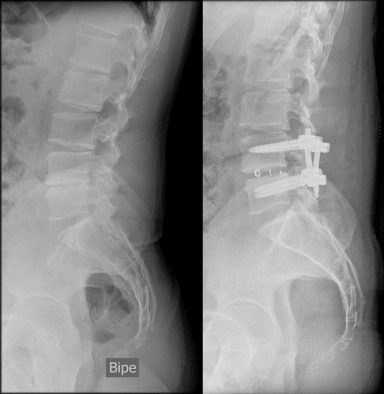

En la zona cervical, grandes osteofitos en C5-C6 y C6-C7 posteriores que protuyen en el canal medular produciendo una estenosis foraminal bilateral, y anteriores que protuyen hacia el esófago, por lo que me realizan una artrodesis cervical, quitando todo el osteofito posterior.

Las vértebras L4-L5, totalmente colapsadas, y apófisis transversas impactando en la cresta iliaca, dieron el resultado final de una cojera permanente, por lo que me realizan una artrodesis lumbar con OLIF.

Antes de la cirugía lumbar, conseguía correr con mi visible cojera y fuertemente medicado, en la categoría de Paratriatlón PTS5.